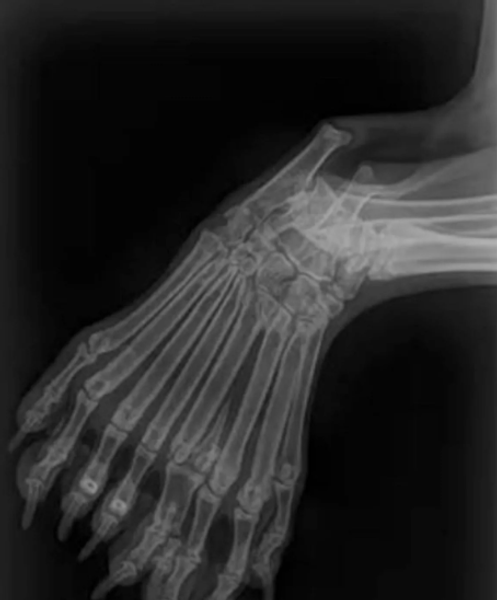

Цуценя Белла народилося з 5 лапами та 9 пальцями | Фото: Wisconsin Humane Society

Завдяки рентгенівським знімкам було виявлено, що у Белли також нестандартна будова іклів, зайві кістки, зокрема стегнова, дві великогомілкові та дві малогомілкові.

За словами ветеринарів, така патологія називається димелія й полягає в дублюванні певних кісток. Вони називають Беллу "справжнім єдинорогом як тілом, так і духом" через її рідкісну анатомічну особливість, а також стверджують, що це перший задокументований випадок димелії саме у собаки.